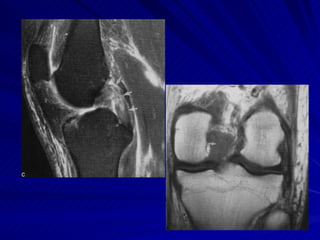

Joelho O estudo do joelho por RM é seguramente o método de imagem mais eficiente para demonstrar a anatomia e as eventuais alterações degenerativas e/ou decorrentes de traumas nesta articulação.

LIGAMENTOS CRUZADOS LCA – eminência intercondiliana da tíbia Porção medial do côndilo femoral lateral LCP – mais forte e mais curto Fossa intercondiliana posterior Porção lateral do côndilo femoral medial

LIGAMENTOS E TENDÕES Tendão do Quadríceps Reto femoral, vasto intermédio, vasto medial e vasto lateral – pólo superior da patela Fusão vasto medial e lateral Ligamento Patelar Pólo inferior da patela – tuberosidade anterior da tíbia